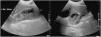

The ultrasound revealed a distended gallbladder of some 15 × 6 cm, with abundant heterogeneous intravesicular content without dilation of the bile duct (Fig. 1).